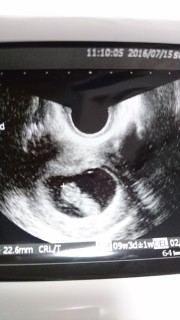

前回、前々回と2回続けて流産してしまったので、今回も健診の日はとても緊張しました。2、6㎜としっかり大きくなってくれてて、ほっとしました。